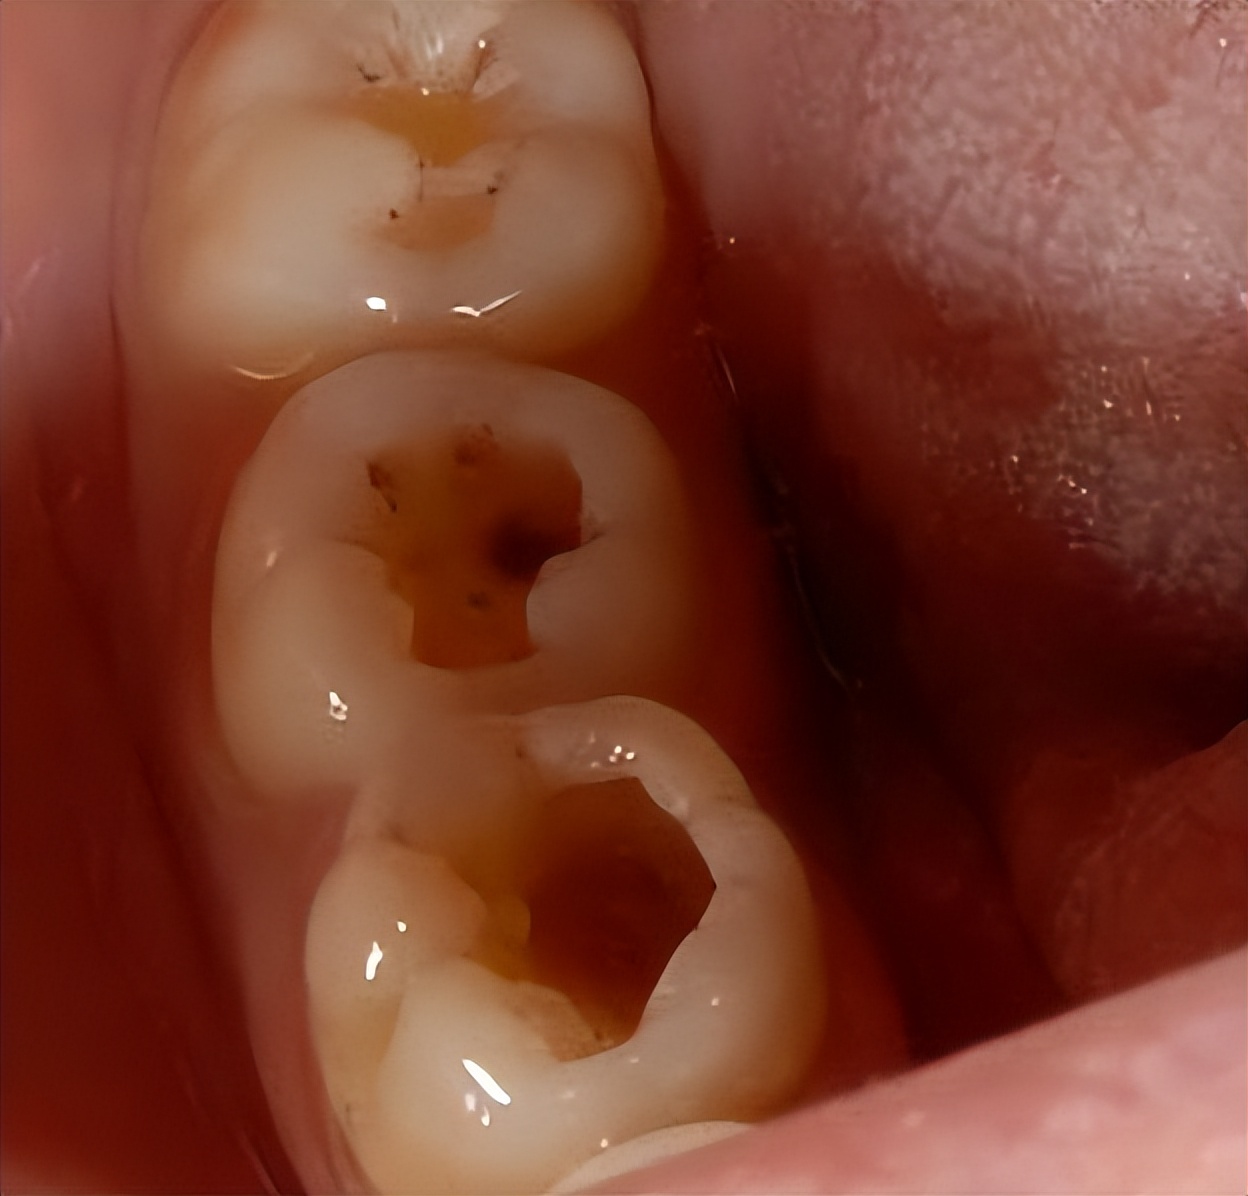

比如这样的:

这样的: